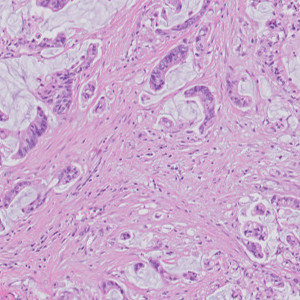

Figure 3

Zooming in, the largest metastasis is reviewed in detail.